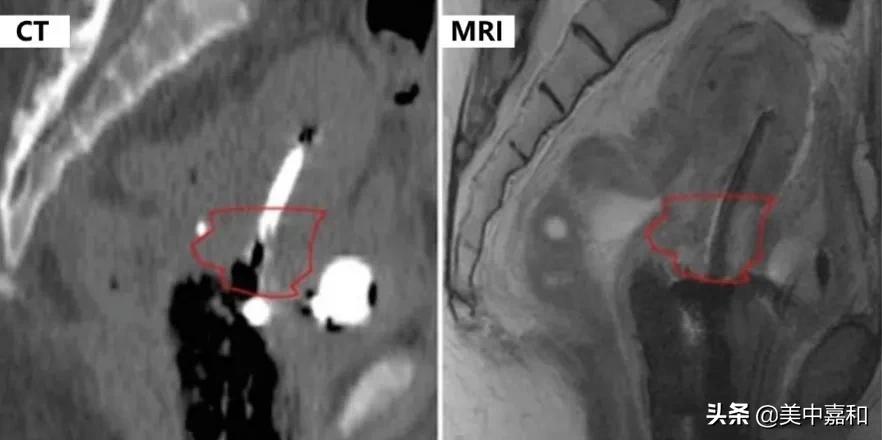

目前国内部分医院仍然采用二维后装治疗,存在靶区脱漏、病灶周围正常组织受量过高、副作用大等缺点,往往容易导致患者肿瘤复发。我院引进先进的瓦里安高剂量率后装机(图 1),利用 MRI 图像引导调整布源、勾画肿瘤靶区,优于传统的 CT 图像引导,能提供更高的软组织分辨率,更好地区分肿瘤与正常组织(图 2),使靶区剂量更加精准,从而提高肿瘤的局控率,并有效减轻膀胱、直肠等周围组织的损伤,降低膀胱炎、直肠炎等并发症的发生率,改善患者的生活质量。

▲ 图 2 宫颈癌后装治疗患者 MRI 图像与 CT 图像对比